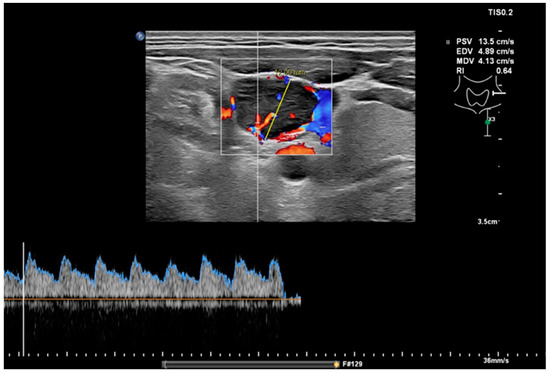

Figure 1.

MFI of peripheral vascularity in a patient with oropharyngeal SCC. At cytology metastasis SCC, MFI shows a strong peripheral vascularity which indicates malignancy; fatty hilum sign is absent.

Figure 2.

Measurement of the RI in the same node as in Figure 1 with a value of 0.64, which would indicate a benign node.